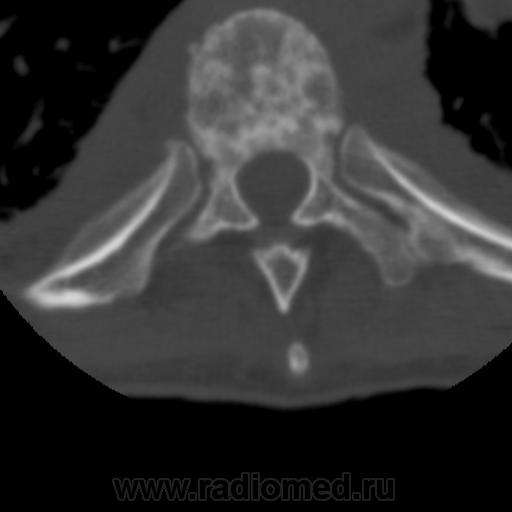

Молодой человек около 30 лет. Из анамнеза известно, что в мае этого года поступает в п\п с диагнозом двухсторонней пневмонией, после дообледования направили в туб. диспансер, к сожалению первых снимков не нашел, есть архив КТ.

Поставил:Туберкулезный спондилит, патологический перелом.

Такая картина сейчас:

Раиль, получается, что сначала появился натечник, а потом разрушился позвонок... Так? Я бы на первое место поставила сепсис, гематогенный (если не контактный...) гнойный спондилит, склеротические поражения позвонков выше и ниже патологического перелома тоже не подходят для туб.спондилита. По КТ не могу исключить сочетание с туберкулезом, но такое количество мелких и средних полостей, преимущественно субплеврально, более характерно для септических эмболов. Есть ли данные по клинике, анализам крови, мокроты? Есть ли динамика самих полостей? Для септических эмболов характерна быстрая динамика с образованием тонкостенной полости. ВИЧ? Подождём еще мнений, может, я не права.

Спондилит есть, да, с патологическим переломом, но вряд ли туберкулезный. А в легких - септическая эмболия. Пациент не наркоман, часом? Вообще, социальный тип?

А. натечник не хилый...